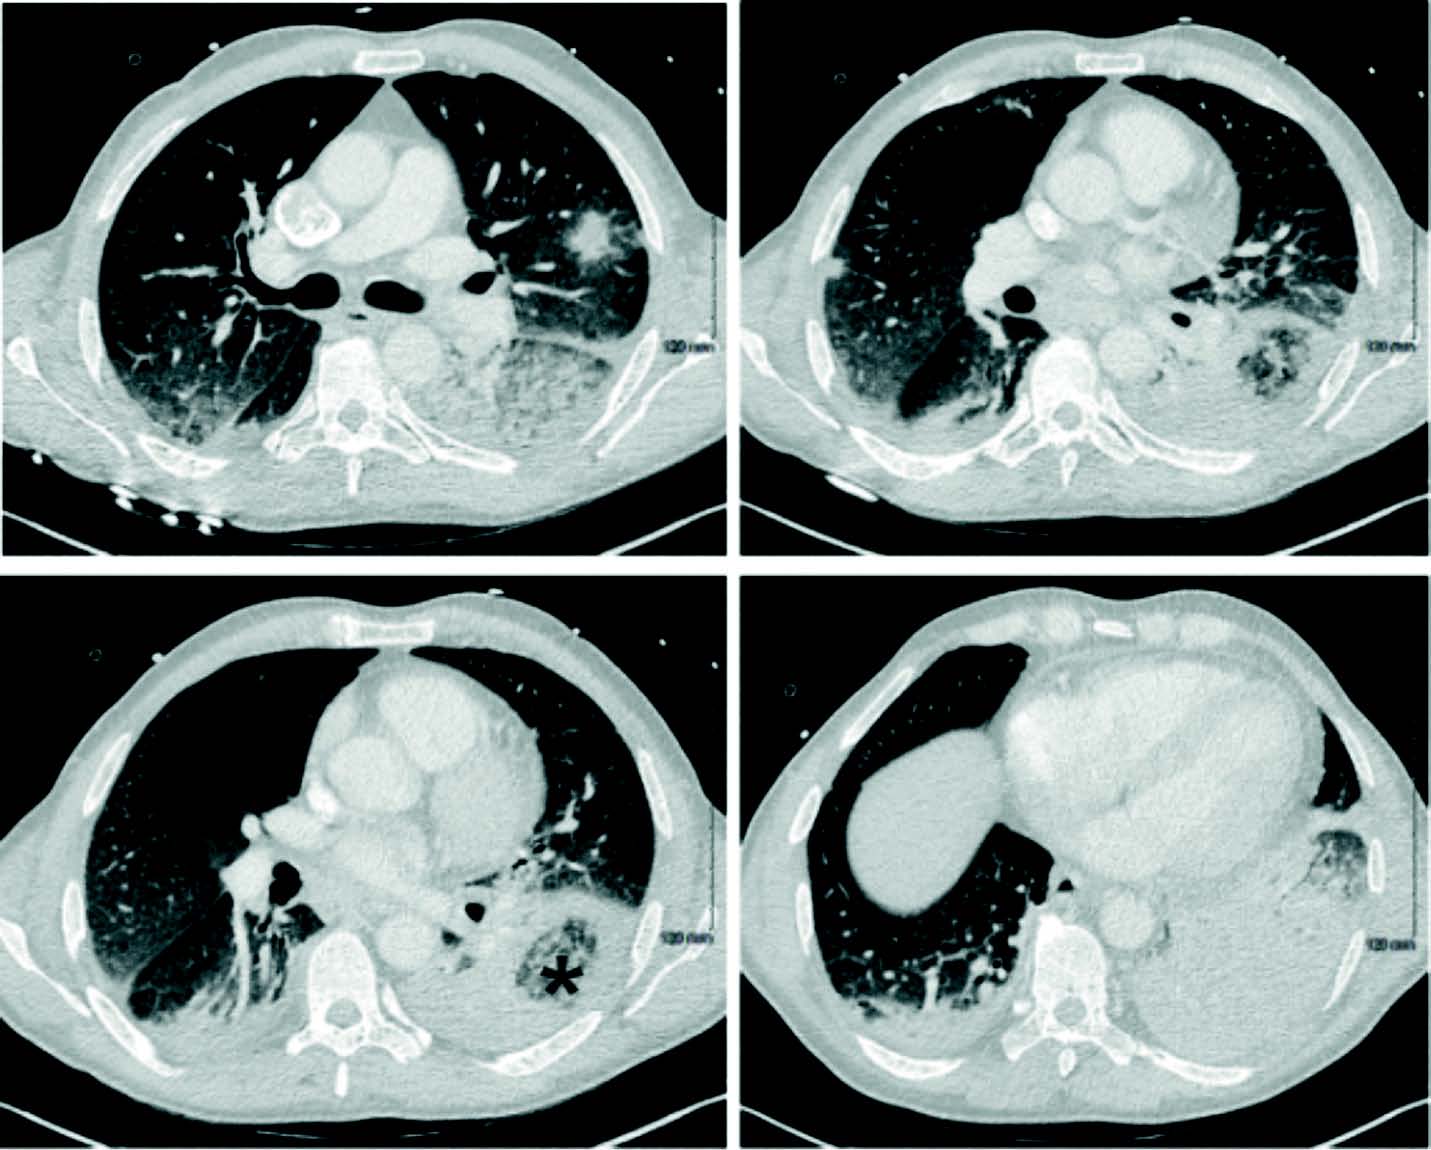

Le scanner thoracique (figure 1) ne retrouve que quelques plages de condensation lobaire supérieure droit antérieure et lobaire moyen, et lobaire inférieur gauche associées à des micronodules centrolobulaires et du verre dépoli. Par ailleurs, il n'y pas d'anomalie au niveau des sinus et abdominopelvien.

Figure 1. Scanner thoracique à J24 d'aplasie